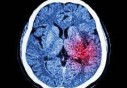

accident vasculaire cérébral : Un travail stressant augmente le risque

Après le tabac et l'hypertension, il faut désormais ajouter le stress au travail dans la liste des facteurs qui favorisent le risque d'accident vasculaire cérébral (AVC).

On savait déjà qu'un AVC sur quatre est directement en lien avec le tabac et que l'hypertension est un facteur de risque important. Grâce à une méta-analyse d'une demi-douzaine d'études antérieures pilotée par le Dr Dingli Xu de l'Université de Guangzhou, en Chine, on sait désormais que le stress au travail est également un risque important d'accident vasculaire cérébral.

Dans cette étude, publiée sur l'édition en ligne de la revue Neurology, les chercheurs ont découvert que les personnes occupant un emploi à stress élevé avaient 22% de risques en plus de faire un AVC, par rapport à ceux occupant un emploi passif et un risque accru de 58% de faire un AVC ischémique (c'est-à-dire lié à l'obstruction d'une artère cérébrale). En outre, face à cette gestion du stress, hommes et femmes ne sont pas à égalité puisque le risque d'AVC est supérieur de 33% chez les femmes.

Un lien entre le travail et le risque d'AVC avait déjà été fait il y a quelques mois par des chercheurs britanniques qui avaient révélé que travailler plus de 55 heures par semaine augmentait de 33% le risque de faire un AVC et de 13% celui de développer une maladie des coronaires par rapport à un travail hebdomadaire de 35 à 40 heures.